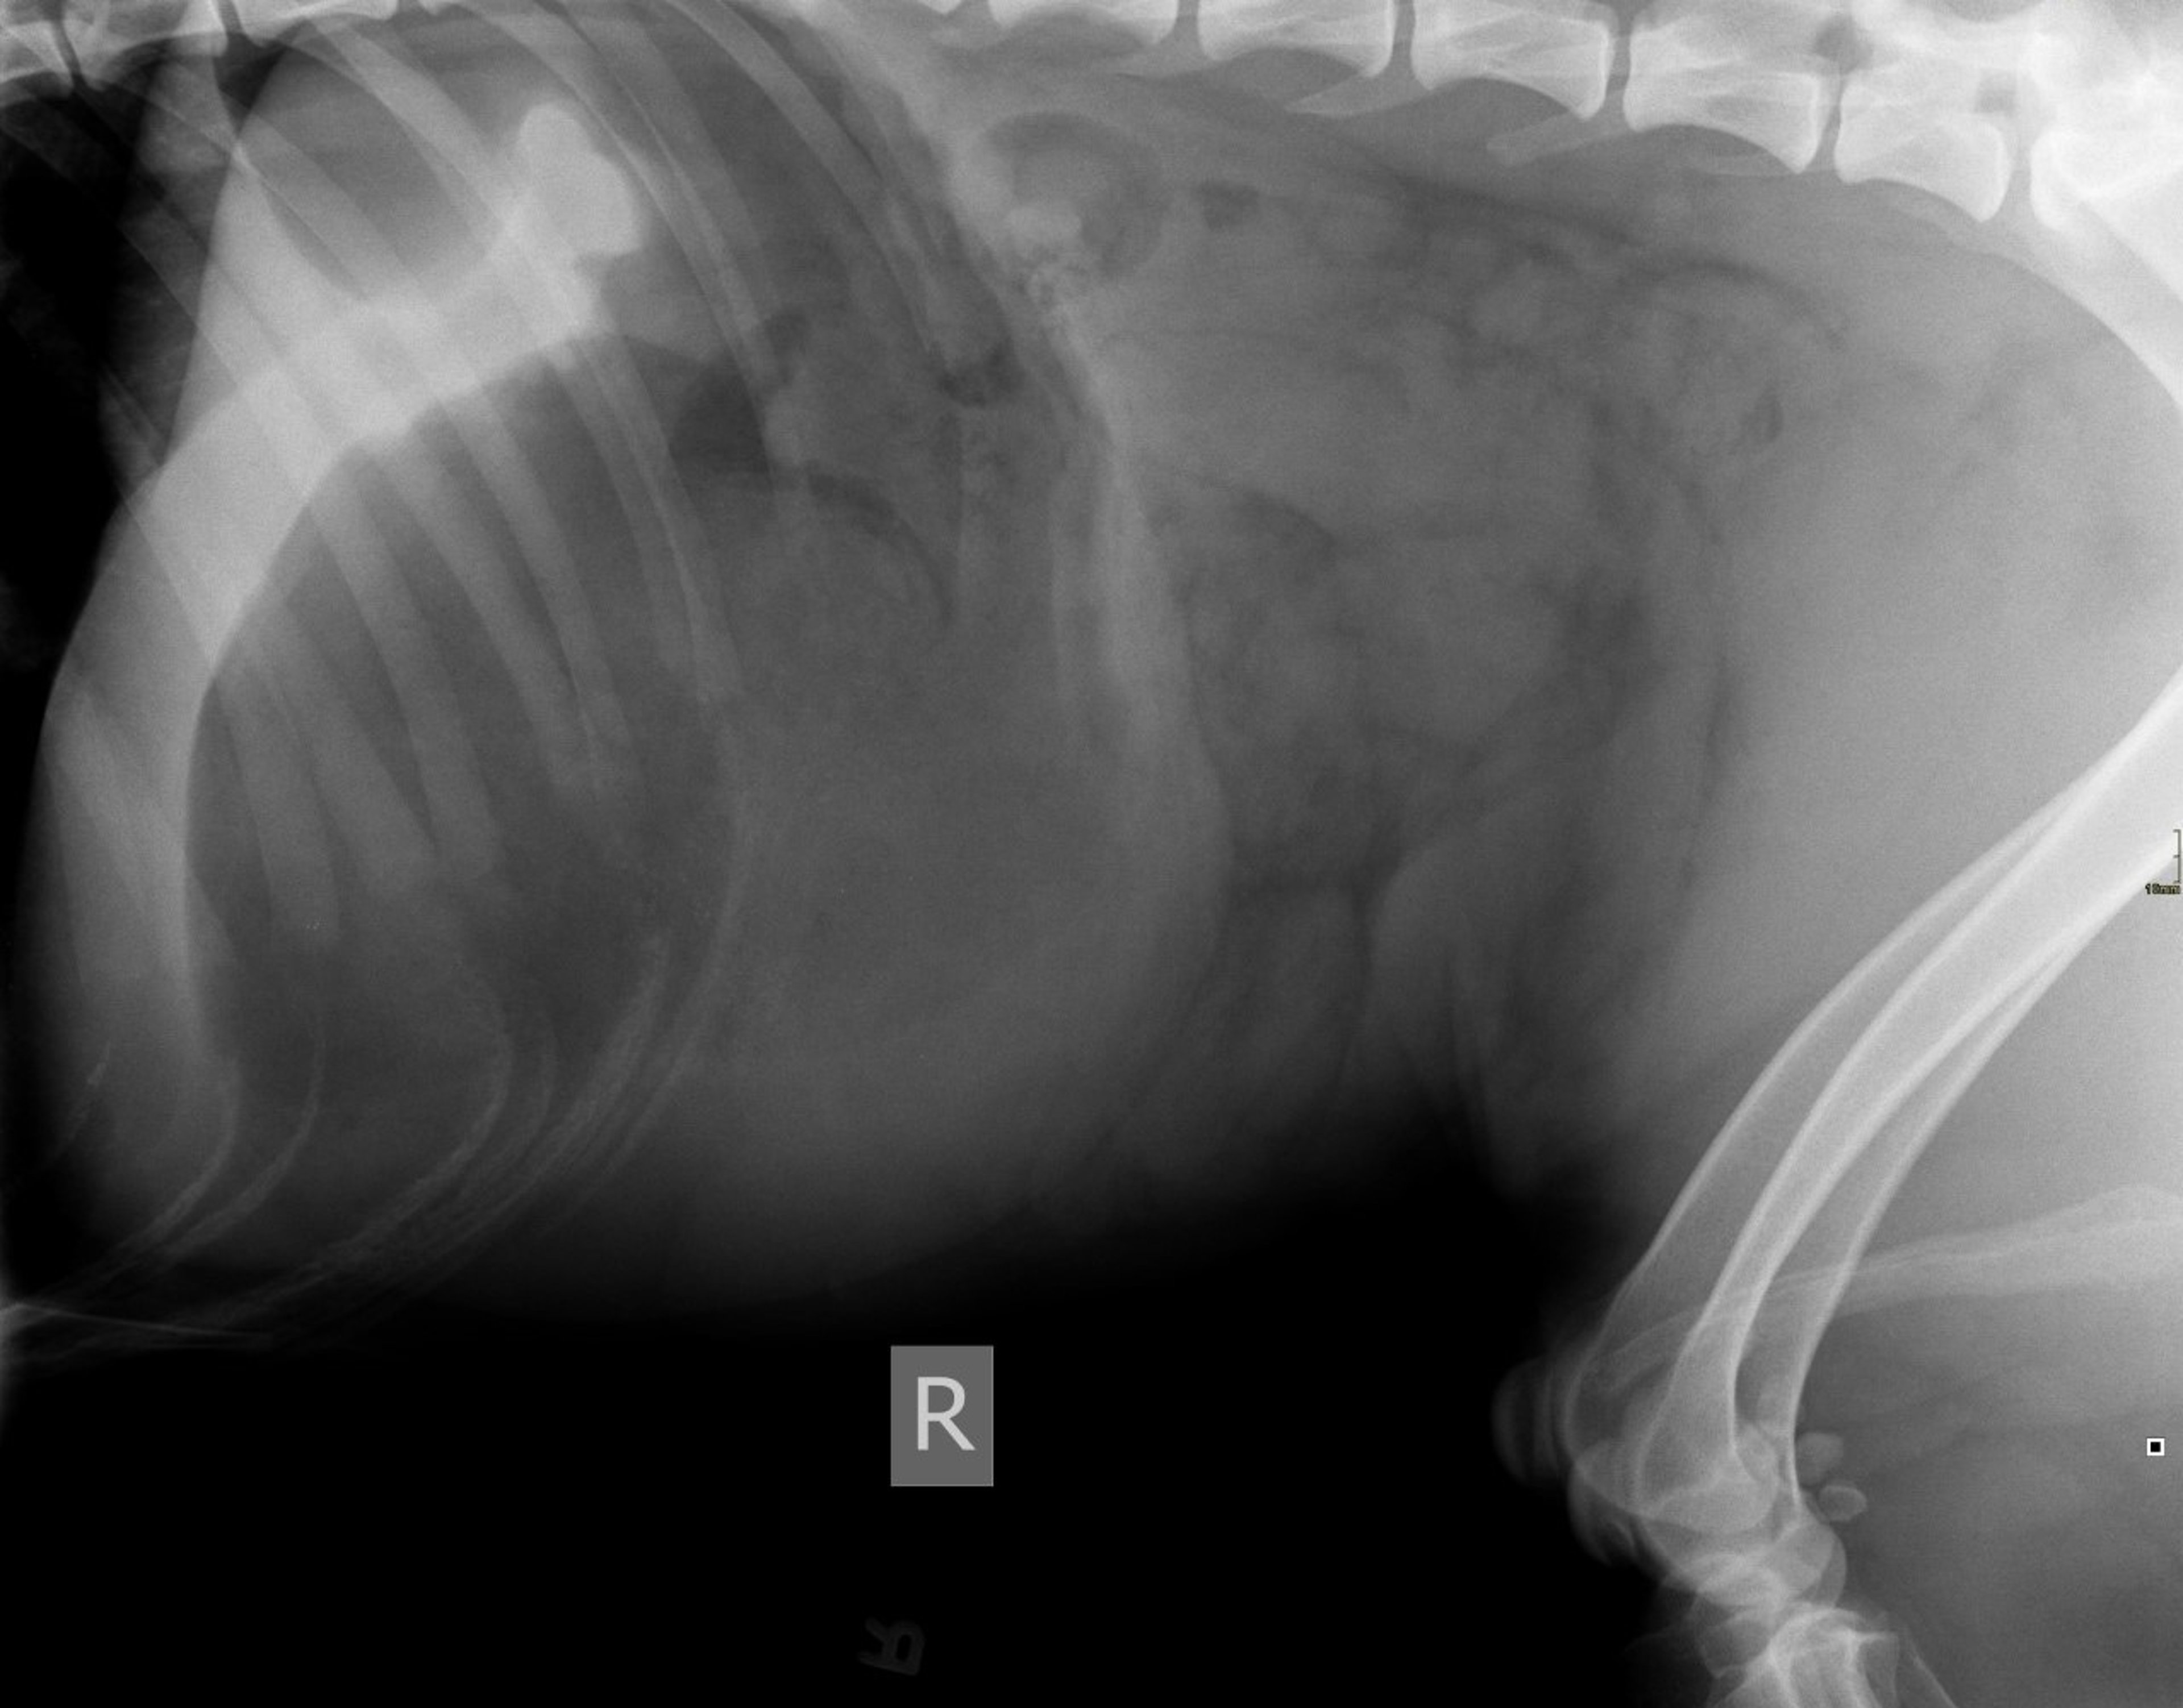

Gastric dilation and volvulus, dog, lateral view

Lateral radiograph of a 2-year-old Great Dane with gastric dilation and volvulus.